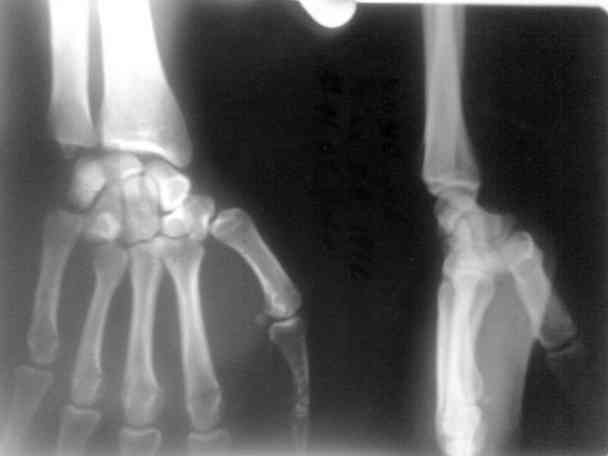

больного я направил в область. его прооперировали. вынесены снимки.посмотрите.

после чего некоторые говорили что это можно было б и неоперировать, а оставить так.

что скажут на этот случай уважаемые колеги форума.

Свежие вывихи 5 пястной или 4-5 пястных костей легко устраняются и могут вестись консервативно в гипсовой лангете. В представленном случае, через 15 дней после травмы, все сделано грамотно. Кстати, такие вывихи встречаются не совсем редко.